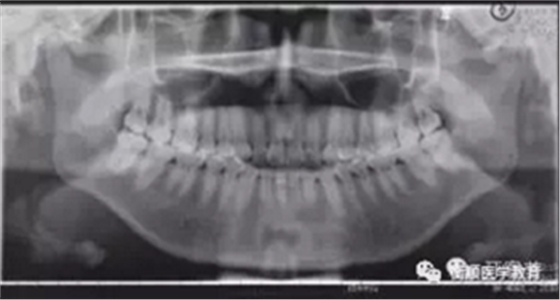

图3 治疗前曲面体层片